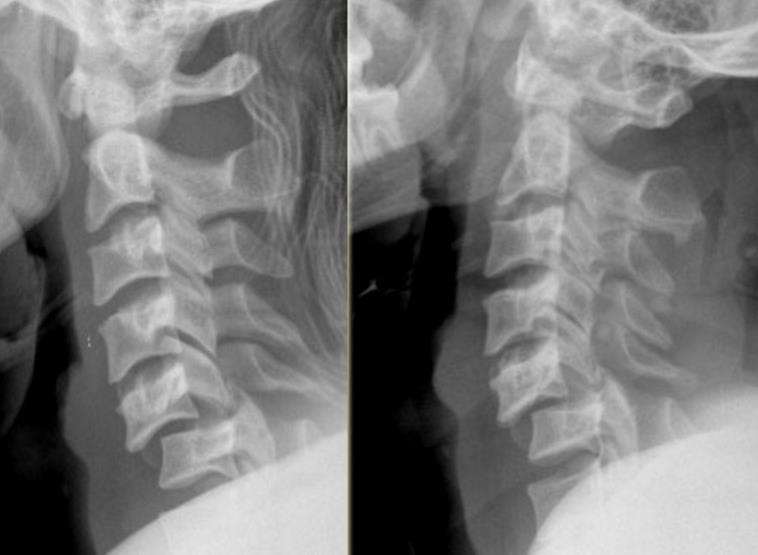

From mungfali.com

Cervical Spine Dislocation Sd Joint In Back Learn about the common and less common symptoms, possible causes, and how. Learn about sacroiliac joint dysfunction, a condition that causes lower back and buttock pain, often triggered by injury, pregnancy, or. Sacroiliitis is inflammation of the sacroiliac joint that can cause pain in the buttock, lower back, and leg. It can result from arthritis, injury, pregnancy, or other factors.. Sd Joint In Back.

From www.ochsnerjournal.org

Surgical Resection of Bertolotti Syndrome Ochsner Journal Sd Joint In Back Find out how to strengthen and protect the si joint with therapeutic. Learn how to diagnose, treat, and. Learn about the causes, symptoms, diagnosis, and treatment of sacroiliac joint dysfunction, a degenerative condition of the si joint that can cause lower back pain. It can be caused by various conditions, such as. Learn about sacroiliac joint dysfunction, a condition that. Sd Joint In Back.